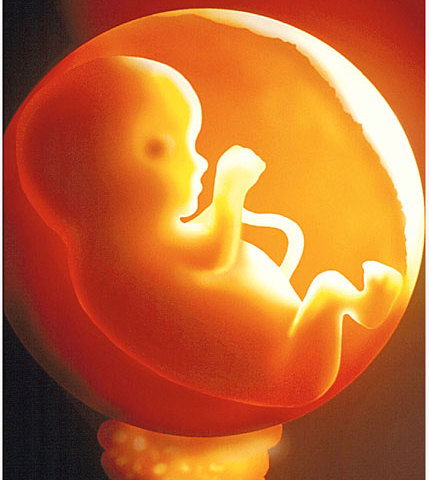

Cathétérisme interventionnel foetal

Cathétérisme interventionnel foetal